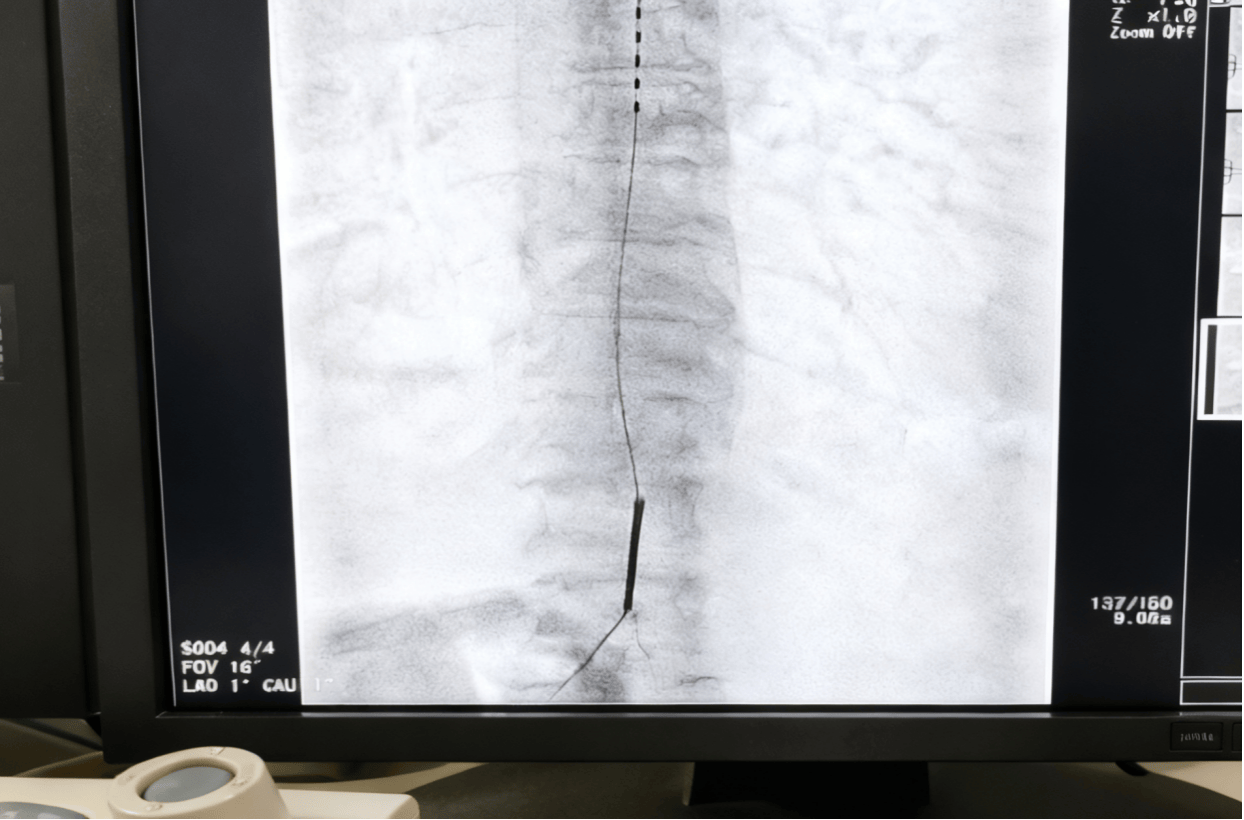

郭宇鹏主任团队为潘奶奶实施了脊髓电刺激电极植入术。这是一种微创的神经调控技术,通过穿刺将细小的电极植入脊髓特定节段,释放电脉冲阻断疼痛信号上传。